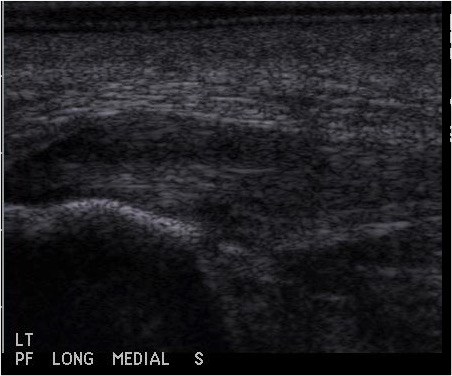

With the advent of musculoskeletal ultrasound, we can effectively diagnose plantar fasciopathy with a high degree of specificity and individually design treatment plans for the level of pathology present in the patient.10 High-resolution sonography allows the practitioner to grade the level of degeneration. Then one should tailor treatment to the level of tissue degradation. For example, sonograms can clearly reflect different levels of severity, requiring different treatment approaches ideally for optimal results. Those practitioners who do not assess the level of tissue degeneration with high-resolution diagnostic ultrasound are pretty much forced to use a cookie-cutter approach as they do not really know what they are treating. Visualization is everything from diagnosis to surgical technique.

The study by Monto and colleagues illustrates the power of regenerative medicine for a degenerative condition. This is why fewer EPFs are necessary at this time. By implementing amniotic tissue allograft (stem cells), I have found more profound effects in treating plantar fasciopathy. While I reserve EPF for patients in a IVB or IVC category on the Barrett Plantar Fasciopathy Ultrasound Grading System (see left), I still recommend intervening with ultrasound-guided partial plantar fasciotomy with amniotic tissue allograft, even for those patients who are likely to need an EPF.